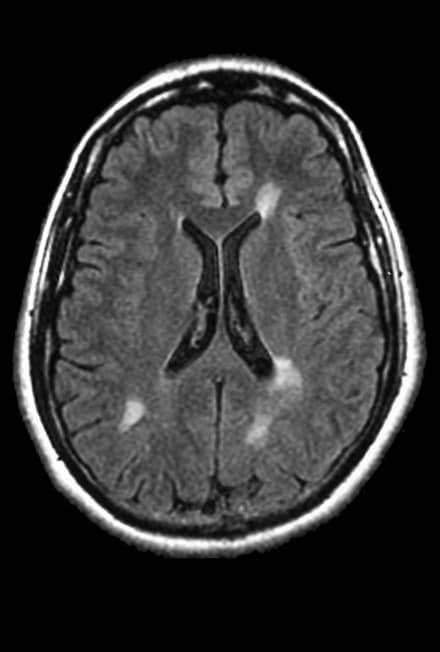

BrainTale’s study represents a significant breakthrough in the differential diagnosis of parkinsonian syndromes, involving a carefully selected cohort of 189 subjects. Among these participants, 92 were diagnosed with Parkinson’s Disease (PD), 45 with Multiple System Atrophy (MSA), and 42 with Progressive Supranuclear Palsy (PSP). Utilizing calibrated diffusion tensor imaging (DTI), BrainTale’s platform analyzed the participants’ brain data to extract diffusion markers, which serve as quantitative indicators of white matter integrity. This advanced MRI technique provides detailed insights into neurodegenerative processes, forming the foundation for an accurate diagnostic model.

The extracted diffusion markers were then analyzed using a supervised learning classification model designed to differentiate between PD, MSA, and PSP based on their unique diffusion profiles. The effectiveness of this model was evaluated through receiver operating characteristic (ROC) curve analysis, a robust method for assessing diagnostic accuracy. The study achieved an impressive average area under the ROC curve (AUC) of 0.87 ± 0.05, indicating high diagnostic performance. Additionally, the model demonstrated an average specificity of 0.74 ± 0.10 and an average sensitivity of 0.90 ± 0.07, reflecting its ability to accurately identify true cases of PD and reduce false positives.